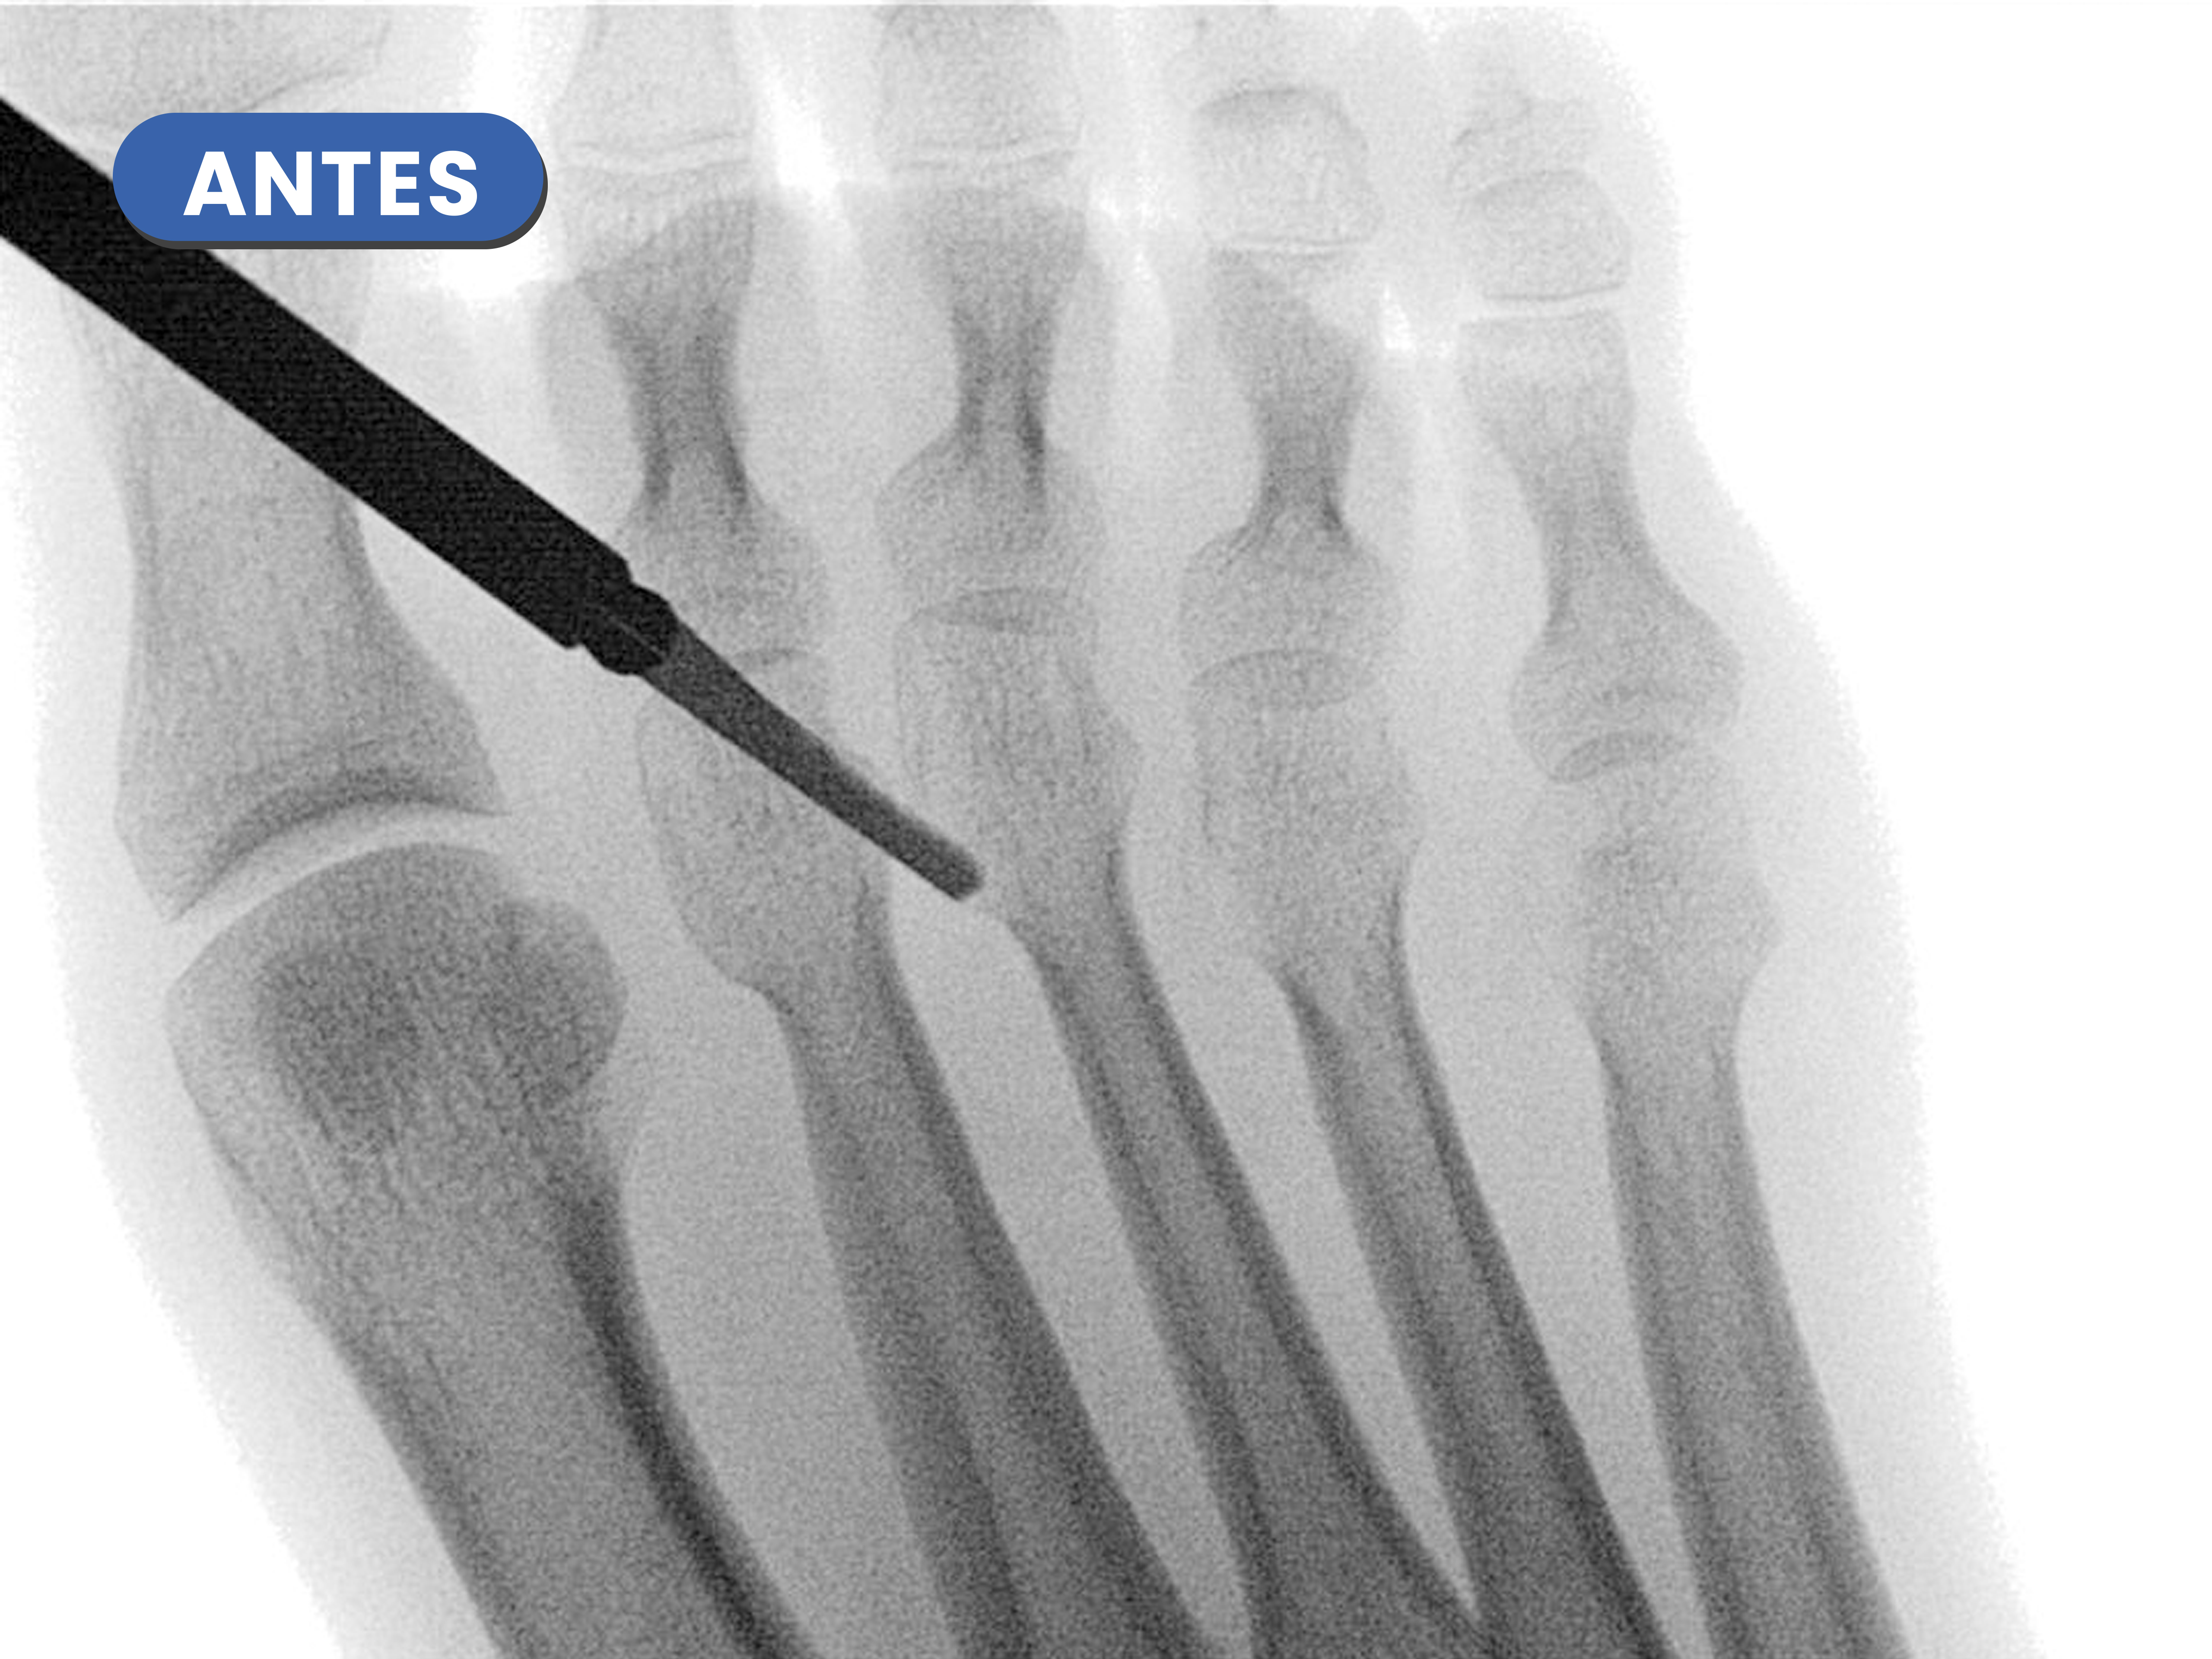

Casos reales resueltos con Cirugía de Mínima Incisión (CMI)

Te mostramos casos reales resueltos mediante cirugía de mínima incisión por el Dr. Rubén Lorca y su equipo.

Mueve las flechas para visualizar el antes y después.

En este caso realizamos una osteotomía acortadora del tercer metatarsiano al ser más largo estaba creando una sobrecarga en la zona, se puede visualizar como disminuye de tamaño en la imagen de después de la cirugía.